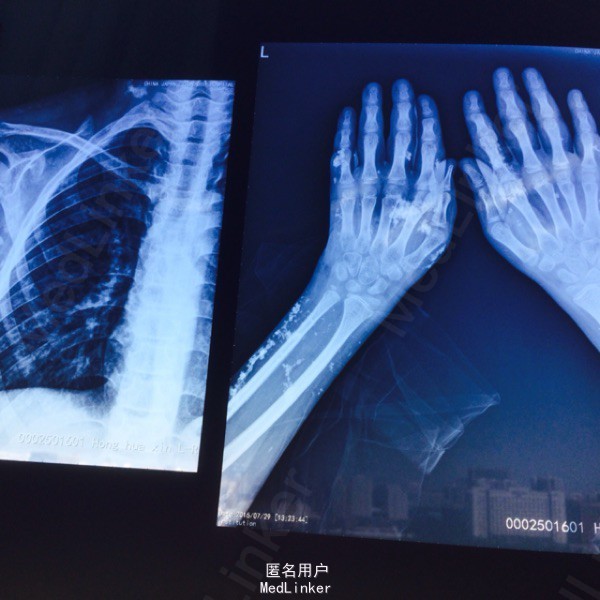

面部可见褐色皮疹及色素沉着。全身多处皮下硬结节。四肢近端肌力2+级。 行四肢X线检查提示广泛皮下钙化。 炎症指标血沉CRP明显升高,肌炎抗体谱 EJ OJ PM阳性。